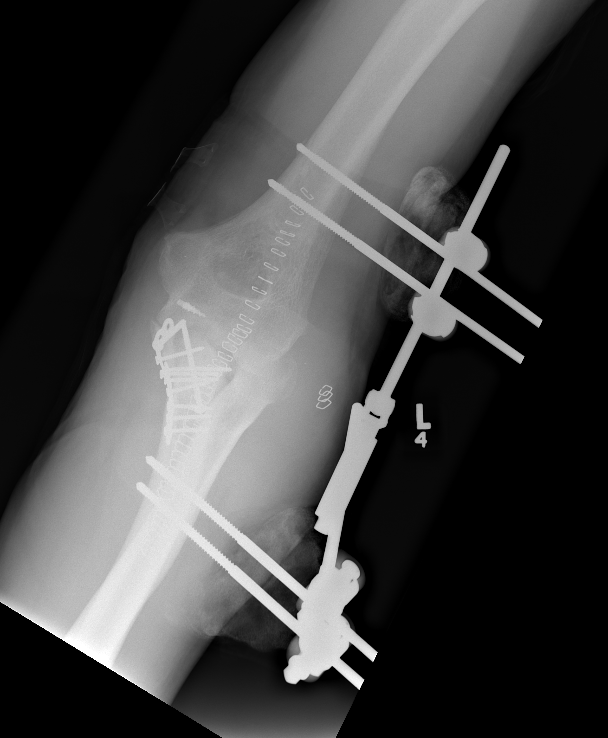

Internal joint stabilizer

IJS Elbow Stabilization System

Concept

Dynamic internal fixator

Technique

Crescenzo et al JSES Rev technique PDF

Results

- 24 patients treated with IJS-E

- 1/24 redislocated - coronoid deficient

Heifner et al J Hand Surg Glob 2023

- systematic review of 171 elbow dislocations treated with IJS-E

- implant failure 4%

- recurrent instability 4%